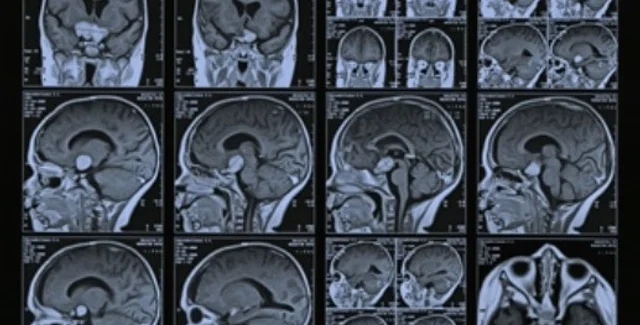

Группа китайских ученых под руководством Хао Лэя из центра магнитно-резонансных исследований в городе Ухань сканировали мозг 17 взрослых людей, у которых была выявлена интернет-зависимость, и сравнили результаты с данными 16 здоровых людей, передает РИА-Новости со ссылкой на Independent.

Результаты исследования, которые могут пролить свет на поведенческие проблемы и содействовать в развитии новых способов избавления от зависимости, выявили поражение белого вещества головного мозга в областях, отвечающих за эмоциональную обработку данных, принятие решений и когнитивный контроль. Аналогичные изменения белого вещества головного мозга были зафиксированы при других формах зависимости, в частности, при употреблении алкоголя и кокаина.

Чтобы выявить нарушения в мозге у взрослых людей, которые ежедневно проводят много часов в интернете, исследователи использовали магнитно-резонансную томографию. Кроме того, были учтены негативные последствия от многочасового времяпровождения в интернете для личной и общественной жизни.